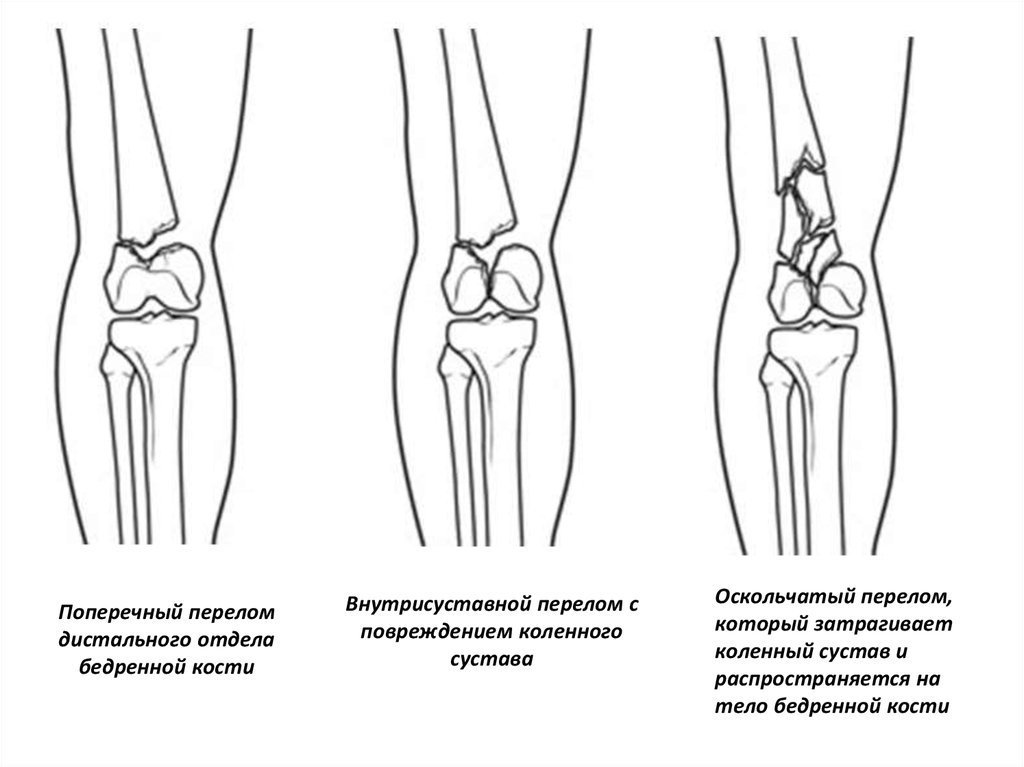

Поперечный перелом

дистального отдела

бедренной кости

Внутрисуставной перелом с

повреждением коленного

сустава

Оскольчатый перелом,

который затрагивает

коленный сустав и

распространяется на

тело бедренной кости